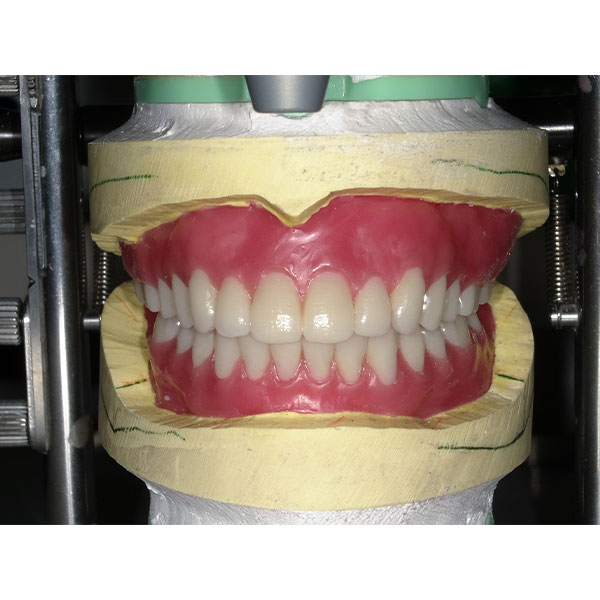

Après la mise en moufle et l'ébouillantage, les dents ont été repositionnées, conditionnées et des caractérisations blanchâtres, pourpres, orange clair, bleues et roses ont d'abord été réalisées au niveau du le bouclier labial. La base a ensuite été incrustée de résines pour prothèses de couleurs orange-rouge, rouge foncé, rouge clair, rose et rose foncé, et tous les polymères à chaud ont été pressés en une seule fois. Après le stockage sous pression, les prothèses finies ont été démouflées, finies et polies. La stratification anatomique tridimensionnelle de VITAPAN EXCELL en masse d'émail, de collet et de dentine avait un aspect absolument naturel dans l'anatomie muco-gingivale reproduite de la base prothétique. Le patient a pu s'habituer rapidement à sa nouvelle prothèse, notamment grâce à l'effet esthétique réussi. Après une courte phase d'adaptation et des corrections minimes dans l'environnement biodynamique, il s'est très bien débrouillé avec sa première restauration prothétique amovible complète et en était pleinement satisfait.